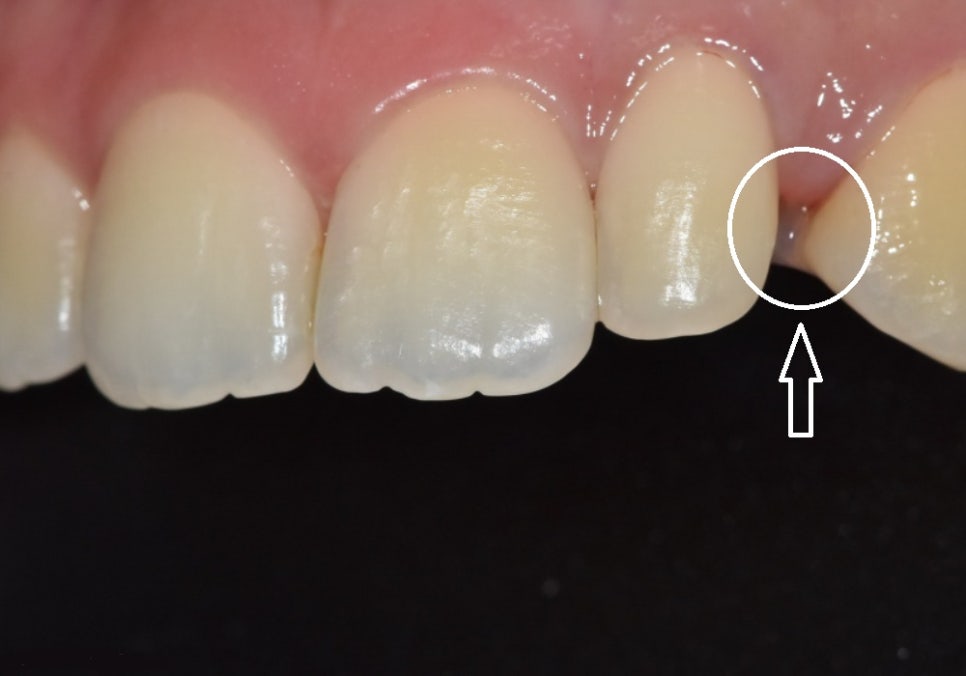

두 번째 환자분은

앞니 크기나 배열 자체는 비교적 안정적이었지만,

한 치아만 크기가 작아

시선이 그쪽으로 모이던 경우였습니다.

이 역시

한 개의 왜소치에 해당하는 상태였지만,

첫 번째 사례와는 구조가 달랐습니다.

앞니와 송곳니 사이가 멀어,

이미 어느 정도 공간이 확보돼 있었고,

왜소치로 인해 공간이 비어 있는 상태

앞니 전체의 크기와 배열도

전반적으로 균형이 잘 잡혀 있었습니다.

즉,

전체가 어색한 상태라기보다

한 지점만 살짝 비어 보이는 구조였습니다.

이런 경우에는

241102

문제가 되는 치아 한 개만

라미네이트로 개선해도

인상에 충분한 변화를 줄 수 있습니다.

실제로 이 환자분도

한 개만 치료했지만,

웃을 때의 인상은

여러 개를 바꾼 것처럼

훨씬 안정적으로 보이게 되었습니다.